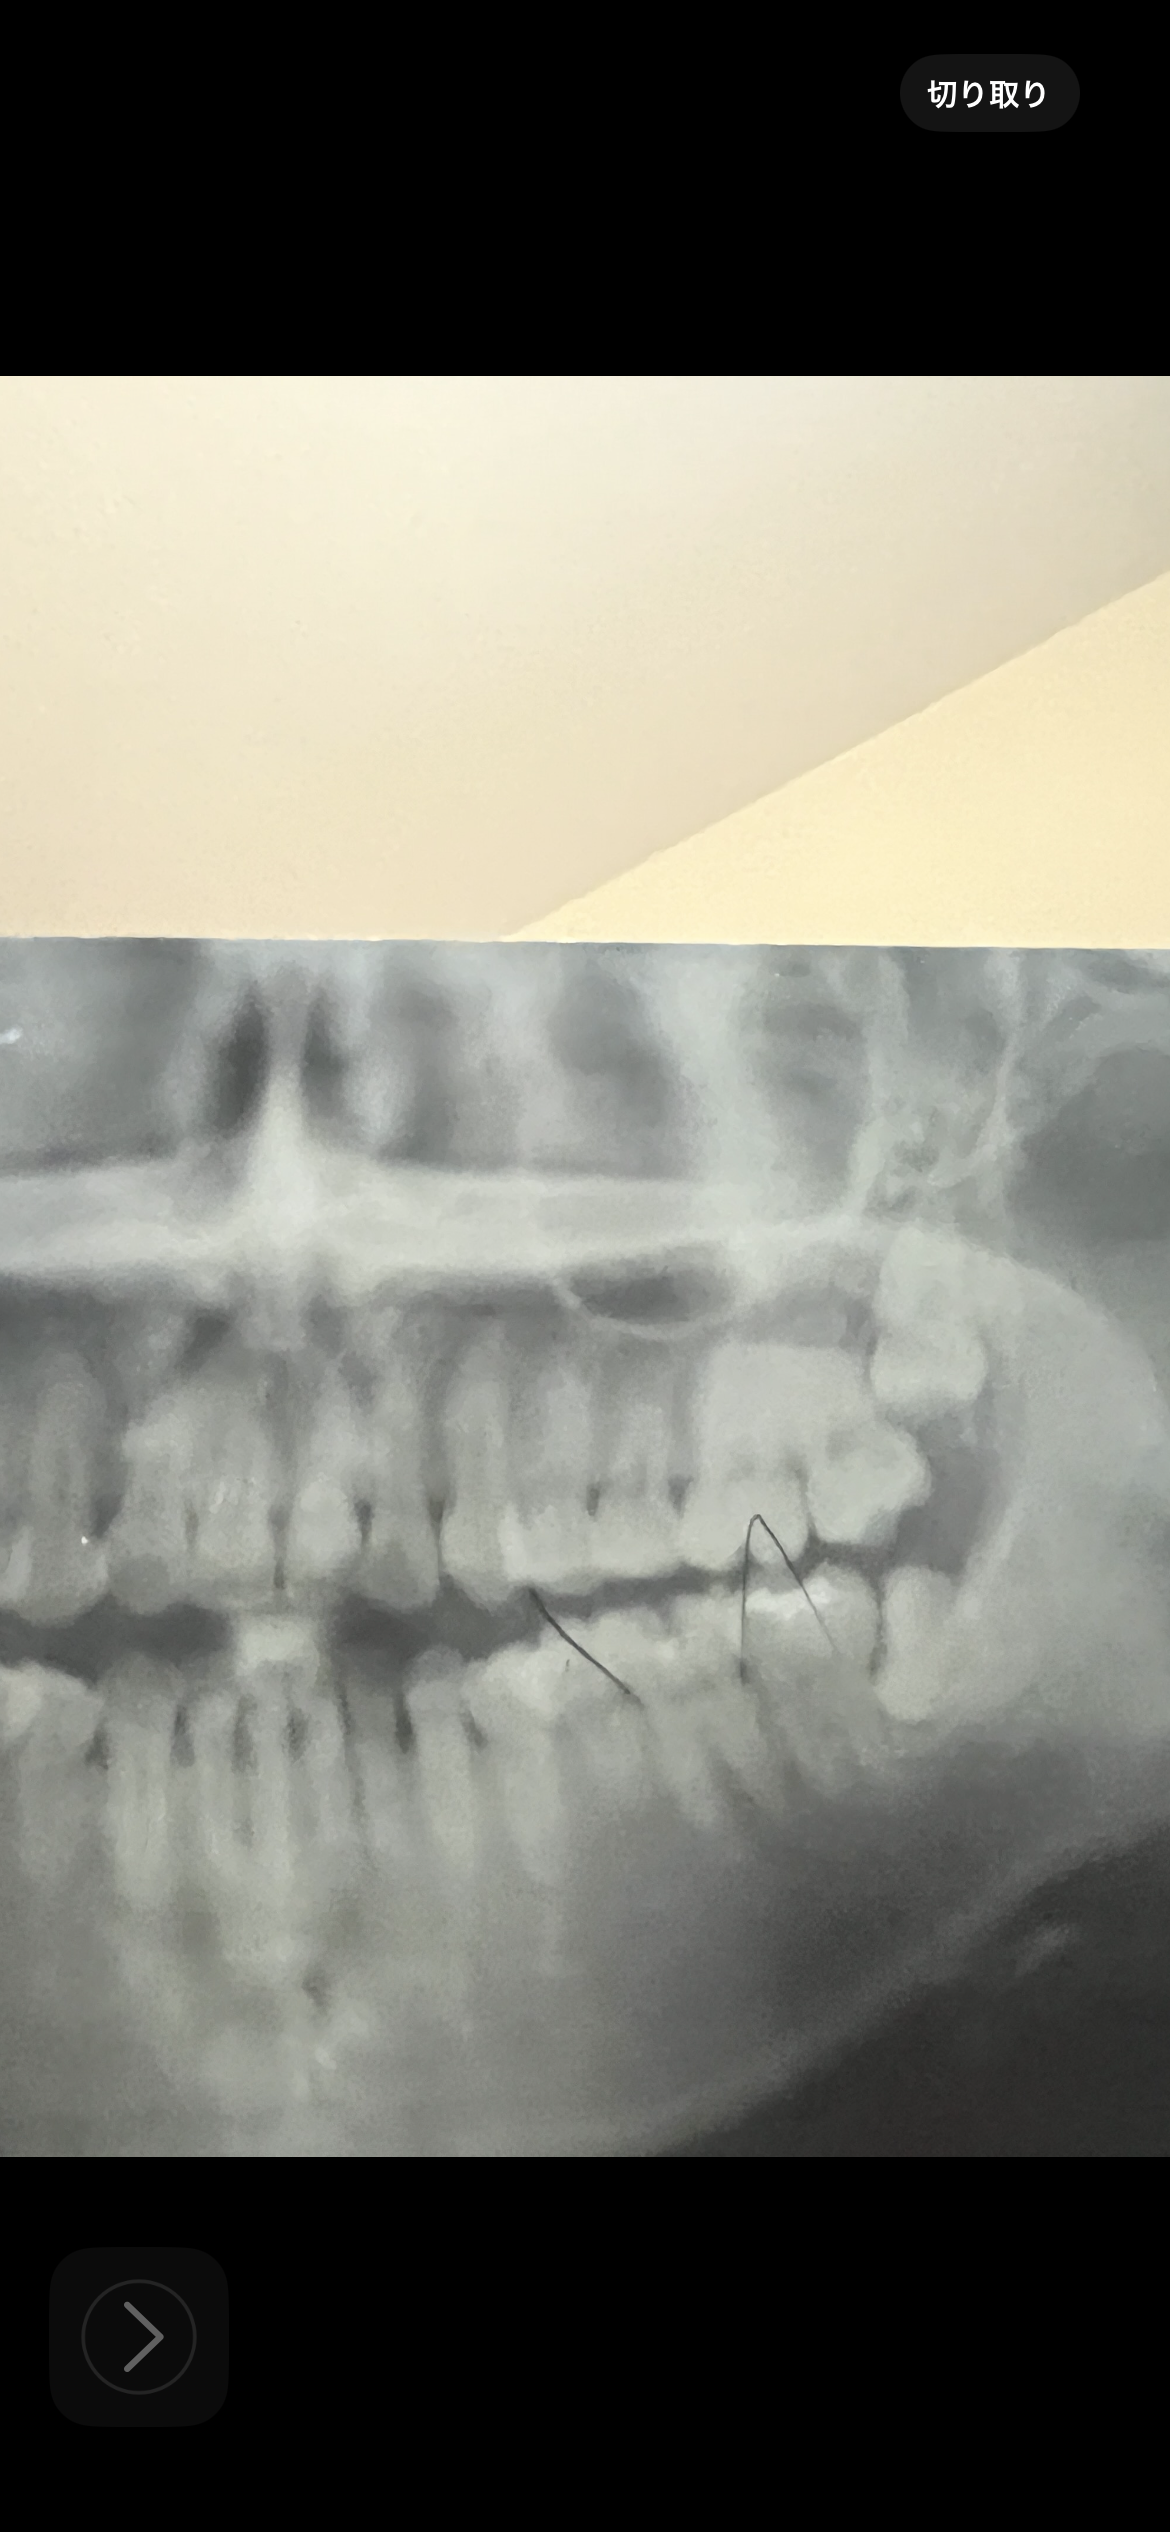

後鼻漏や鼻づまりがあります。歯性上顎洞炎の可能性はありますか?